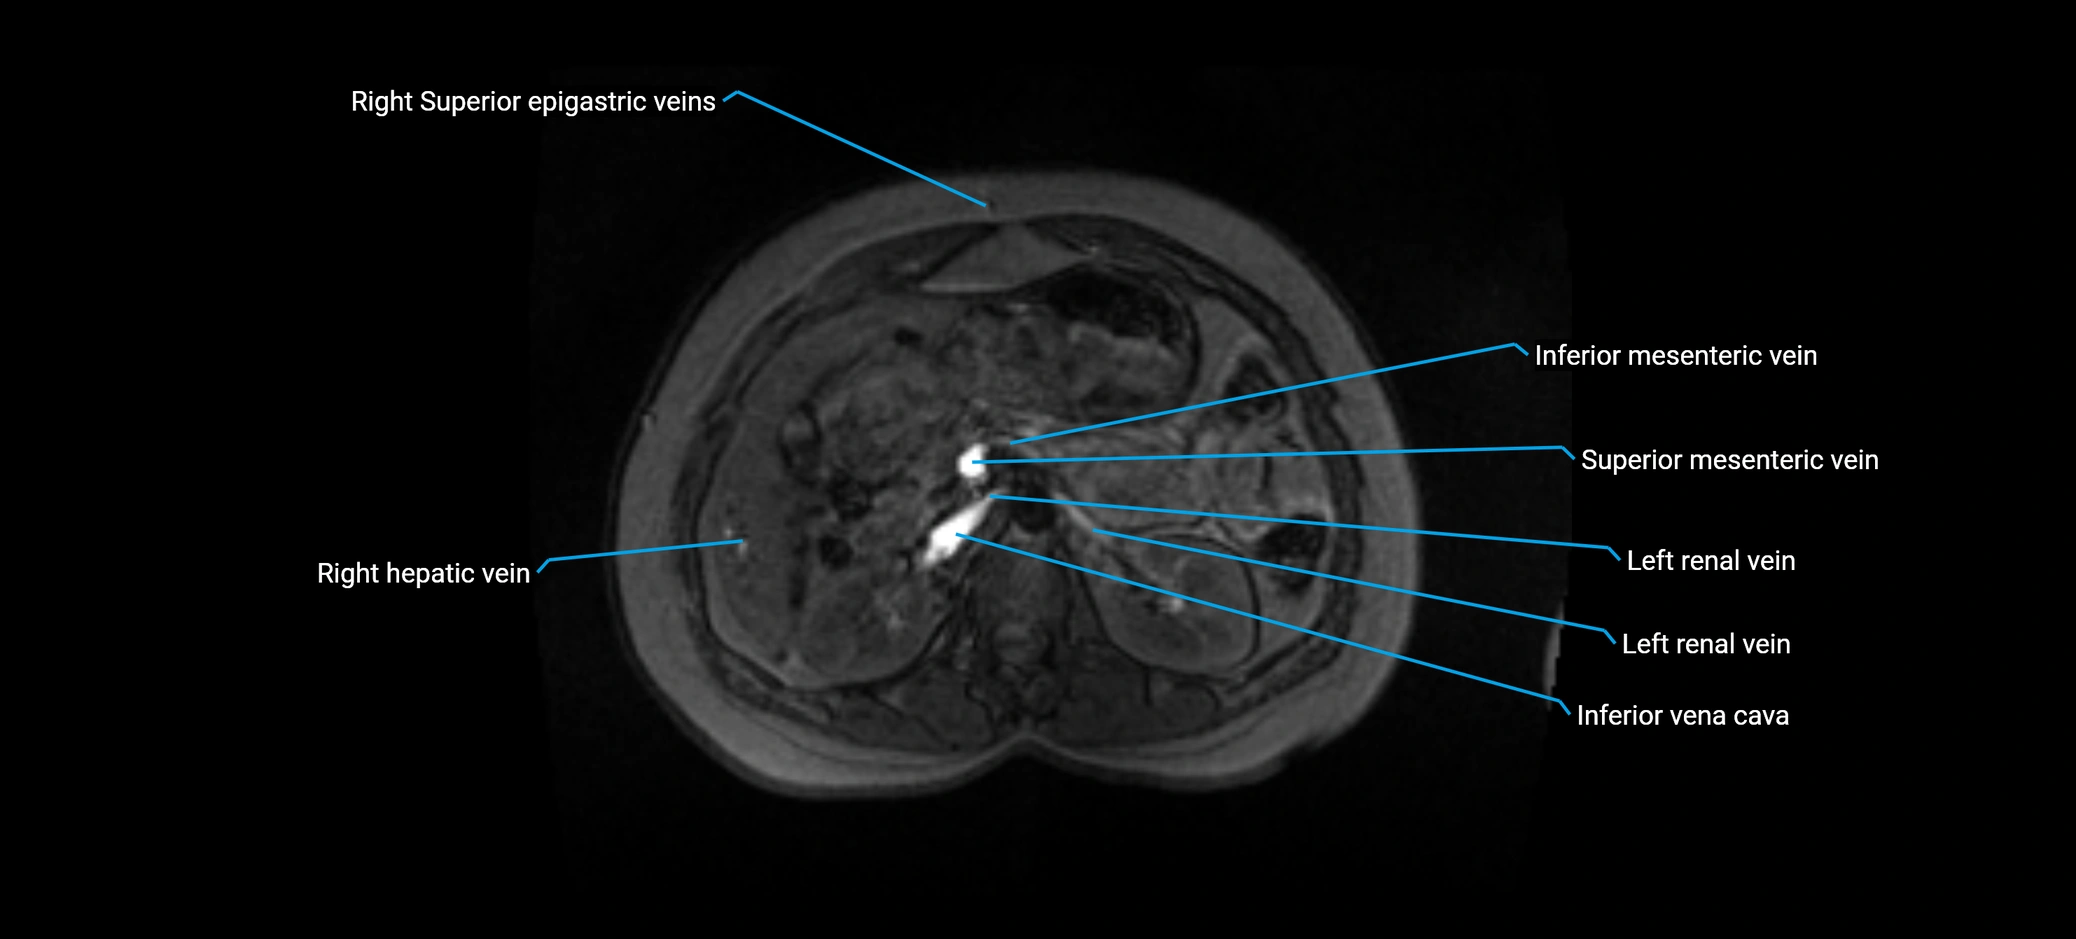

MRI image

image